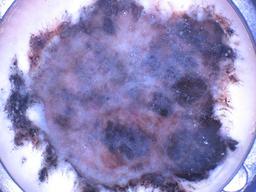

BRAAFF-Annotated Acral Lesions Dataset (BALD)

The BRAAFF-Annotated Acral Lesions Dataset (BALD): A curated set of dermatoscopic images of acral melanoma and nevi from various sources.

Müller C, Tschandl P, Rinner C, Kyrgidis A, Koga H, Moscarella E, Apalla Z, Di Stefani A, Kobayashi K, Lazaridou E, Longo C, Phan A, Saida T, Sotiriou E, Tanaka M, Thomas L, Zalaudek I, Argenziano G, Lallas A, Kittler H. The BRAAFF-Annotated Acral Lesions Dataset (BALD): A Curated Set of Dermatoscopic Images of Acral Melanoma and Nevi from Various Sources. J Invest Dermatol. 2025 Jan 17:S0022-202X(25)00021-1